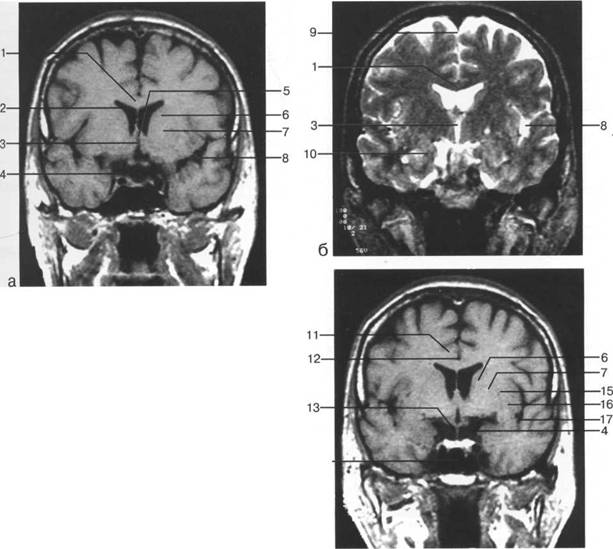

Задняя череп 13513u2010n 85;ая ямка представляет собой часть основания череп 13513u2010n 72;, ограниченную централь

Следует отметить, что в настоящее время оптимальным методом исследования структур задней череп 13513u2010n 85;ой ямки является МРТ, которая, в отличие от КТ, лишена артефактов от кост

Мозжечок заполняет практически весь объем задней череп 13513u2010n 85;ой ямки. Его поперечный раз

IV IV IV IV III IV

височная доля; 17 - полушарие мозжечка; 18 - |

Следует остановиться на анатомии подпаутинных пространств задней череп 13513u2010n 85;ой ямки IV 20 мм. Между основанием череп 13513u2010n 72; и нижней поверхностью мозга от большого затылочного отверстия вдоль ската и спинки турецкого седла простирается задняя базальная цистерна. В зави IV